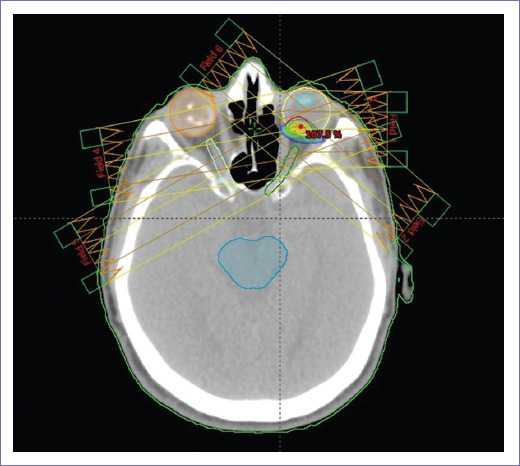

Hombre de 63 años sin antecedentes de importancia con cuadro clínico de cuatro meses de evolución caracterizado por disminución de agudeza visual en ojo izquierdo de manera progresiva. Acude con oftalmólogo, que realiza paquimetría corneal y fondo de ojo izquierdo, reportan tumoración dependiente de retina, 7.47 x 2.36 mm. Se refiere al servicio de oftalmología del Hospital General de México (HGM) y se hace el diagnóstico de melanoma coroideo. Se envió al servicio de radioterapia para tratamiento radical con IMRT, energía de 6 mV, dosis total 50 Gy en 25 fracciones. Inició tratamiento el 11 de junio y terminó el 19 de julio de 2019. Al termino de la RT presentó mejoría de la agudeza visual; al año se mantiene asintomático, agudeza visual conservada y sin datos de actividad tumoral local o a distancia por estudios de imagen. Las figuras 3 y 4 muestran corte transversal y vista 3D de planeación del tratamiento en donde se observan las curvas de dosis y distribución campos de radiación.